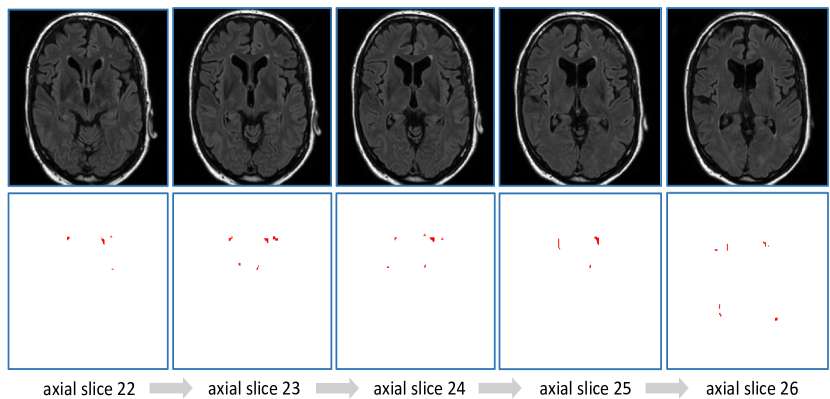

5.1 Why choose 2D architecture

It is noted that there exist several 3D convolutional network architectures for brain tumor segmentation (Kamnitsas et al., 2017b; Havaei et al., 2017). The main motivation of employing 3D architectures is to extract rich spatial and contextual information from tumor/lesion tissue volume. However, in case of WMH segmentation, small lesions with high discontinuity and low contrast are commonly found, which contain poor spatial and contextual information. Furthermore, the imaging resolution along z-direction of the contest images is rather poor, and there exists large variation of spatial resolution as shown in Table 1, which further restricts the use of 3D deep learning models. Figure 8 shows the case 11 in dataset Utrecht, in which small lesions with discontinuity characteristic are observed. Therefore a 2D architecture is chosen for this challenge to explore the texture information at slice level, and to drastically reduce the computational complexity. Data augmentation further equips the 2D model with desired invariance and robustness. It should be acknowledged that, when large clinical datasets are available in future, 3D architectures might help to improve the segmentation performance.